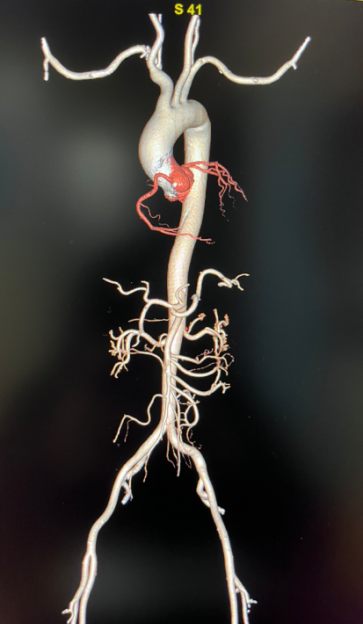

更全面——一站式多部位掃描

設(shè)備擁有16cm寬體等焦寶石探測器,是目前業(yè)內(nèi)最寬探測器,可一次性實現(xiàn)多血管或多器官聯(lián)合掃描。該CT獨有的自由組合一站式聯(lián)合掃描技術(shù),實現(xiàn)不同掃描模式的快速切換,患者只需注射1次造影劑即可快速完成全方位聯(lián)合掃描,如冠脈CTA+頭頸CTA,冠脈CTA+主動脈全程CTA,胸痛三聯(lián)(冠脈CTA+肺動脈CTA+主動脈全程CTA),大幅提升胸痛三聯(lián)征、心腦血管上下肢及胸腹血管病變的檢出率,為讓患者得到及時科學(xué)有效的診療提供了強有力的技術(shù)保障。